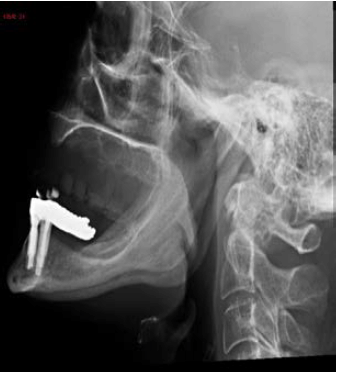

Uma paciente de 60 anos realizou radiografia de seios da face com queixa de cefaleia. Frente às imagens, considera-se que há: